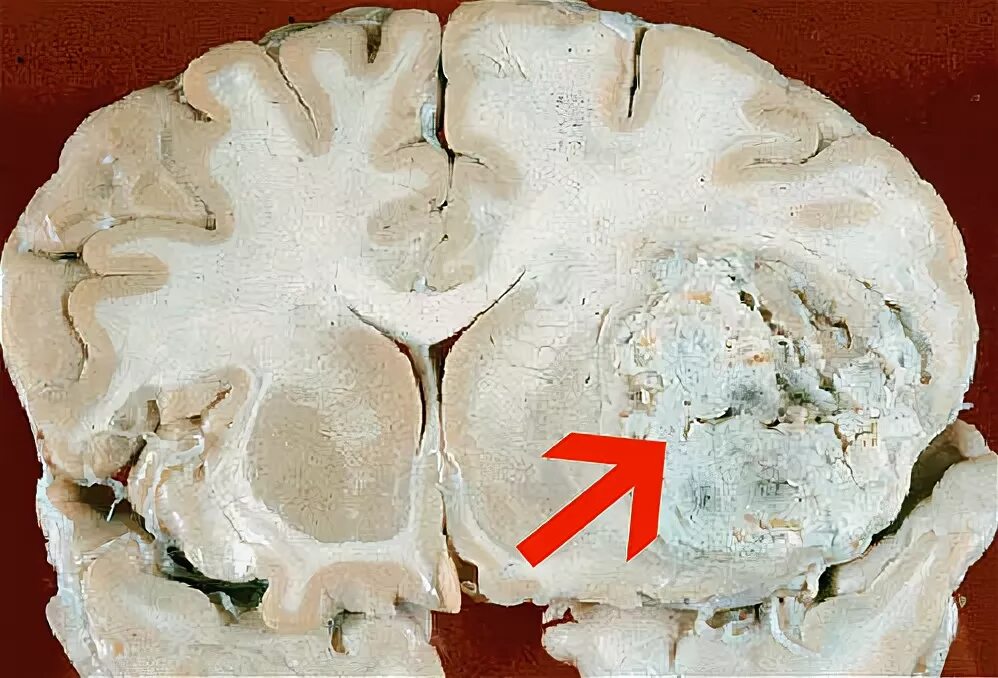

Бластома мозга